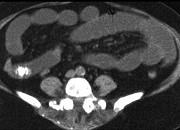

问题 男,30岁,有胆结石病史,近日腹痛、腹胀,CT检查如图,应诊断为 ( )

选项 A.胆石症 B.胆石性肠梗阻 C.肠结核 D.小肠克罗恩病 E.小肠淋巴瘤

答案 B